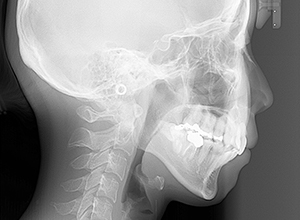

動的治療終了時

FP・IOP

X-Ray

批評・予后 上顎前歯の可及的な後退と臼歯関係のⅡ級を保つためにアンカレッジコントロールはmaximumとしTADを使用してスライディングメカニクスにて前歯遠心移動を行った。また下顎はリンガルからのアプローチであったためその特性を生かし、臼歯のアップライトを速やかに達成して左下5の配列も予定通り行えた。また大幅な前歯の後退に伴い、軟組織の大幅な改善が認められたように思う。